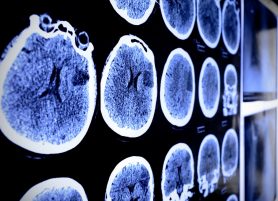

High response rates to a pair of combination therapies point to potentially new options for a group of metastatic melanoma patients who have been largely left out of recent treatment progress – those whose disease has spread to the brain.

A combination regimen of two immunotherapies and another of two targeted therapies each significantly shrank brain metastases in at least 50 percent of patients in separate multi-center clinical trials presented today at the 2017 ASCO Annual Meeting by principal investigators from The University of Texas MD Anderson Cancer Center.

Tawbi reported the unprecedented result that 41 of 75 patients (54 percent) of the patients treated to date in the trial had their brain tumors significantly shrink.  Sixteen patients had a complete response -- disappearance of all tumors.  Importantly, at nine months of follow up, only one of the 41 responders developed disease progression, Tawbi noted, a strong sign of durable response, a hallmark of these drugs when they are effective in patients with metastatic melanoma.

Davies reported 44 of the 76 patients (58 percent) in that group had their brain tumors significantly shrink, and four had a complete response. Similar results were observed in the other three groups in the trials, although those groups were much smaller (16-17 patients per group).